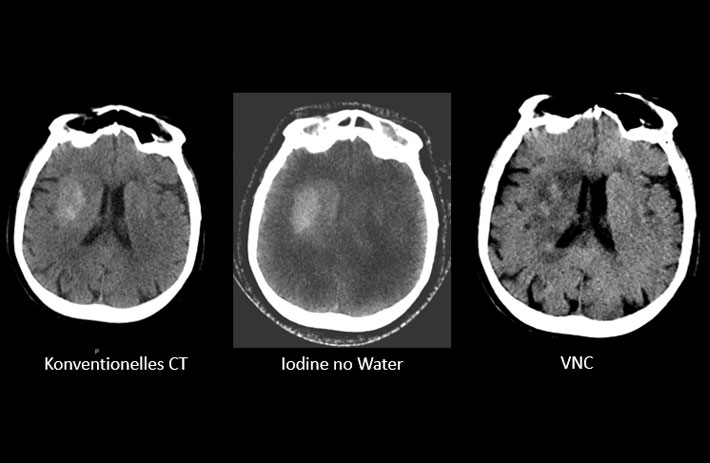

Mit dem Spektral-Detektor-CT werden Spektraldaten automatisch bei jedem Scan erfasst. Die Informationen stehen jederzeit auf der Scankonsole, der CT-Workstation sowie an jedem PACS-Arbeitsplatz zur Verfügung, sodass es nicht notwendig ist, den Patienten erneut zu scannen, bspw. wenn initial zufällige Anomalien festgestellt wurden. Dadurch profitieren Anwender durch eine höhere Diagnosesicherheit und weniger Nachuntersuchungen auf anderen bildgebenden Systemen. Unsere Fallsammlung zeigt, welchen klinischen Mehrwert der Spektral-Detektor-CT in unterschiedlichsten Anwendungsbereichen in der klinischen Routine bringt. Jede Woche gehen neue Fälle live.